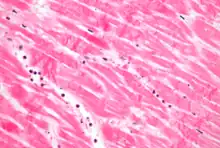

La tinción más utilizada en histología es una combinación de hematoxilina y eosina (a menudo abreviada como H&E). La hematoxilina se utiliza para teñir los núcleos de azul, mientras que la eosina tiñe de rosa el citoplasma y la matriz extracelular de tejido conectivo. Hay cientos de muchas otras técnicas usadas para teñir selectivamente las células. Otros compuestos utilizados para teñir los cortes de tejido incluyen la safranina, el Oil Red O, el rojo Congo, las sales de plata y los colorantes artificiales. La histoquímica se refiere a la ciencia que utiliza las reacciones químicas entre los productos químicos de laboratorio y los componentes de los tejidos. Una técnica histoquímica realizada con frecuencia es la reacción del azul de Prusia de Perls, que se usa para detectar los depósitos de hierro en enfermedades como la hemocromatosis.[2] Recientemente, se han utilizado anticuerpos para teñir determinadas proteínas, lípidos y carbohidratos. La técnica denominada inmunohistoquímica ha aumentado significativamente la capacidad de identificar categorías de células de manera específica con un microscopio. Otras técnicas avanzadas incluyen la hibridación in situ para identificar moléculas específicas de ADN o ARN. Estos métodos de tinción con anticuerpos a menudo requieren el uso de cortes histológicos congelados. Estas técnicas también se llevan a cabo en el laboratorio bajo el control y la precisión de un científico especialista formado en laboratorio clínico (un histólogo). Las cámaras digitales se utilizan cada vez más para capturar imágenes histopatológicas.

Después de un infarto de miocardio (ataque al corazón), no se observa ninguna histopatología en aproximadamente los primeros 30 minutos. El único signo que puede aparecer en las primeras 4 horas es la ondulación de las fibras en el margen. Sin embargo, después se inicia una necrosis por coagulación con edema y hemorragia. Después de 12 horas, se observa cariopicnosis e hipereosinofilia de los miocitos con bandas de contracción necróticas en los márgenes, así como el inicio de la infiltración por neutrófilos. Entre los días 1-3 hay una continua necrosis por coagulación con pérdida de núcleos y estrías, y hay un aumento de la infiltración de neutrófilos en el intersticio. Hasta el final de la primera semana después del infarto, se inicia la desintegración de las fibras musculares muertas, la necrosis de los neutrófilos, y comienza la eliminación de las células muertas en el margen por parte de los macrófagos, que aumenta en los días sucesivos. Una semana después, también se inicia la formación de tejido de granulación en los márgenes, que madura a lo largo del mes siguiente, y hay un aumento del depósito de colágeno y una disminución de la celularidad hasta que la cicatrización miocárdica está totalmente madura, aproximadamente a los 2 meses del infarto.[3]